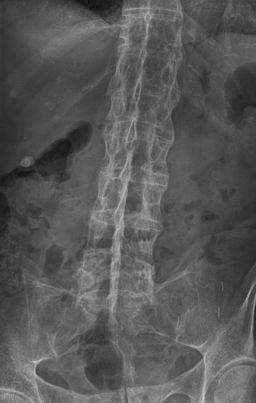

The vertebral bodies may become 'squared'. In later stages, bony bridges (syndesmophytes) form between adjacent vertebrae, there is ossification of spinal ligaments and, in late disease, there may be complete fusion of the vertebral column (bamboo spine).

Bamboo spine

By Stevenfruitsmaak, via Wikimedia Commons